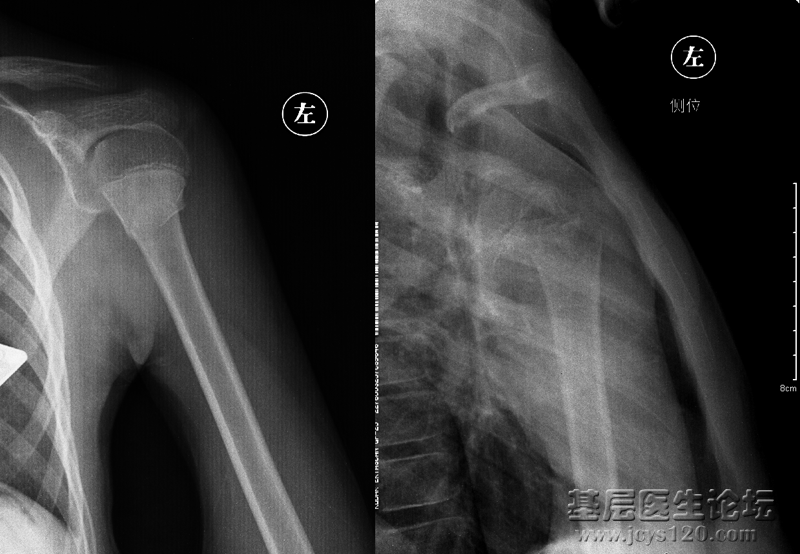

倒霉啊。先说说患者:男,14岁(有怀疑),摔伤 第一次是肩关节正位,是我一个同事照的: 显示肱骨外科颈骨折,患肢悬吊固定一周前来复查,这回是肱骨正侧位: 我照的,正位好说,侧位选取穿胸位,连续失败了 ... 阅读全文>

前几天有一个病人因肩痛在别处行针灸治疗,针灸一次后痛点上移至肩关节岗上肌处,并且疼痛加剧彻夜难眠。前天到县医院检查拍了片子,说是肩关节处长骨头需手术治疗。病人不放心今天又到市医院重新检查拍了片子说是岗 ... 阅读全文>